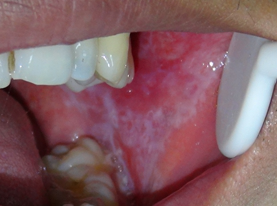

2、口腔扁平苔藓

扁平苔藓发病率高,是一种与多因素有关的疾病,多数患者没有症状,有些患者感觉粘膜粗糙,涩感,烧灼感,遇刺激性食物灼痛,糜烂型者疼痛明显,是一种癌前状态。

主要治疗为:去除局部刺激因素、局部药物治疗+全身免疫调节、中西医结合治疗。我科引进国外先进的水激光,大大提高了治疗效果。